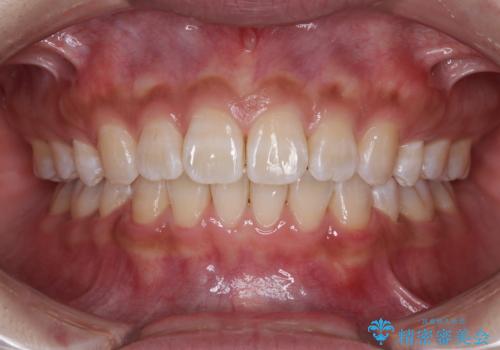

- 上下前歯の叢生を気にして来院された患者様です。

費用を抑え、期間もあまりかけずに治療をしたいとのことで、インビザライン・ライトを用いて矯正治療を行うこととしました。